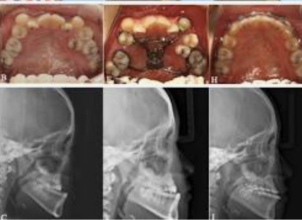

- Pre-surgical Orthodontics: Often needed before the actual surgery takes place. Imaging: X-rays and CT scans are required.

- Planning: Virtual surgical planning is performed on a computer, along with model surgery.